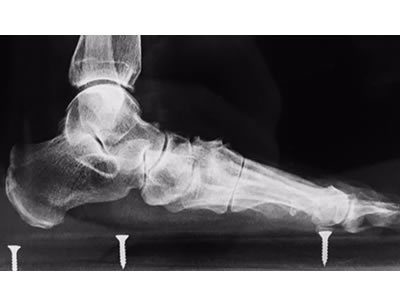

Typical Flatfoot Deformity

Non Arthritic Flatfoot Deformity

Correction of Deformity with Tendon Augmentation/transfer and Bone Grafting